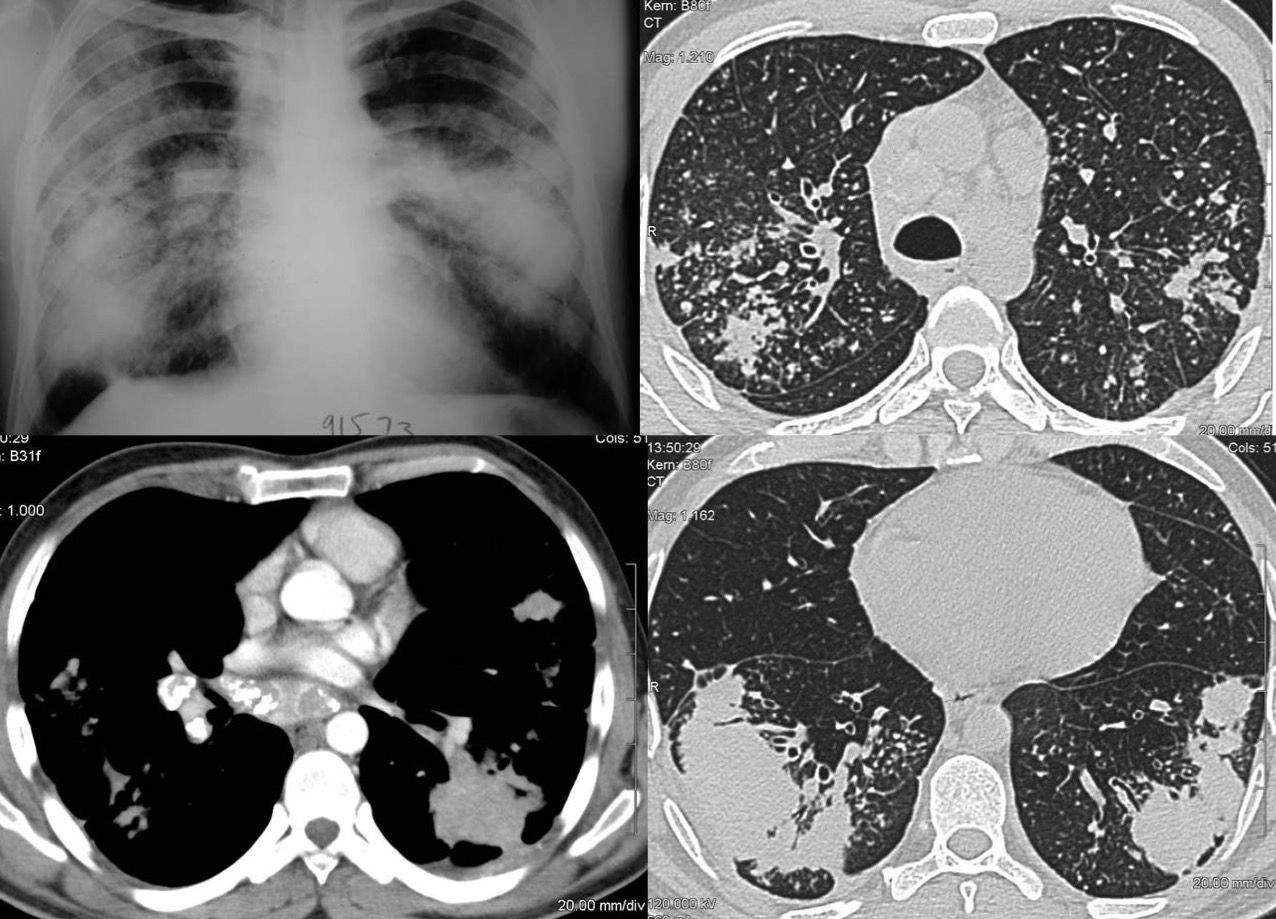

Case 29: The Slow Long Burn of Sarcoidosis Paid Members Public

The changing patterns of disease over 16 1/2 years in this patient with biopsy proven sarcoidosis